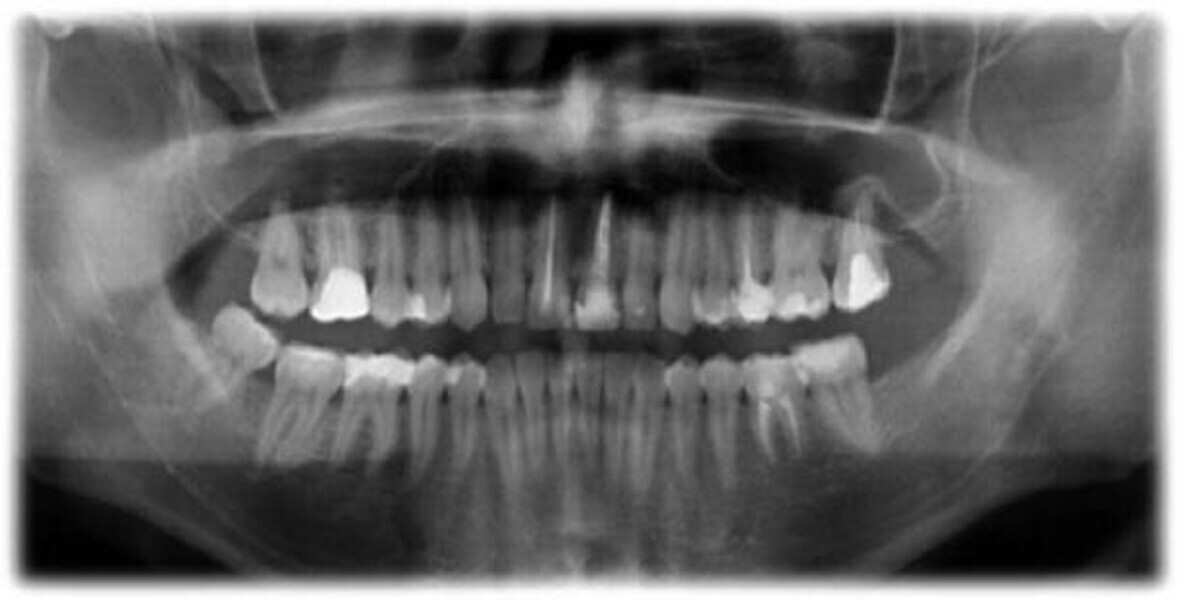

Leczenie endodontyczne autogennego przeszczepu zęba